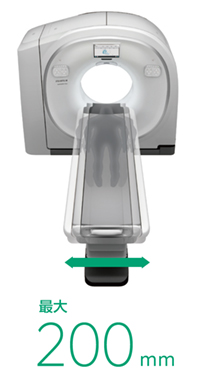

特長<4>

広々とした800mm開口径と200mm横スライド寝台

SCENARIA Viewは広々とした800mmの開口径を実現。さらに,横への可動域200mmを有する寝台により撮影部位をスキャンFOVの中心に配置することで空間分解能が向上します。